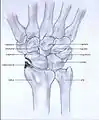

Post-traumatic osteoarthritis can be classified into four stages.[1][6] These stages are similar between SLAC and SNAC wrists. Each stage has a different treatment.

- Stage IV: the osteoarthritis is located in the entire radiocarpal joint and in the intercarpal joints. It also may involve the distal radio-ulnar joint (DRUJ).

Stage IV